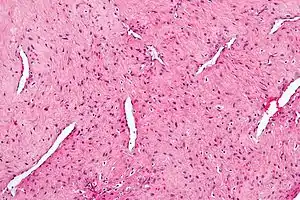

| Micrograph of a nasopharyngeal angiofibroma H&E stain. | |

Nasopharyngeal angiofibroma, also known as juvenile nasal angiofibroma, is a non-cancerous, locally aggressive vascular tumor of the nasopharynx.[3]

If nasopharyngeal angiofibroma is suspected based on physical examination (a smooth vascular submucosal mass in the posterior nasal cavity of an adolescent male), imaging studies such as CT or MRI should be performed. Biopsy should be avoided as to avoid extensive bleeding since the tumor is composed of blood vessels without a muscular coat.